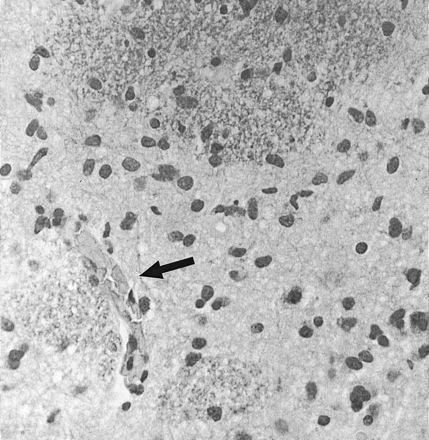

Histopathologic analysis showed a diffusely infiltrating process with no evidence of vascular hyperplasia or necrosis in any of the specimens (Fig 3).

High-power view of histopathologic section of gliomatosis cerebri (hematoxylin-eosin with Luxol fast-blue stain, original magnification ×200). There are moderately pleomorphic glial cells in a diffusely infiltrating pattern with relative preservation of underlying cytoarchitecture. No evidence of vascular proliferation or necrosis is seen. A small collapsed vascular structure (arrow) is noted.